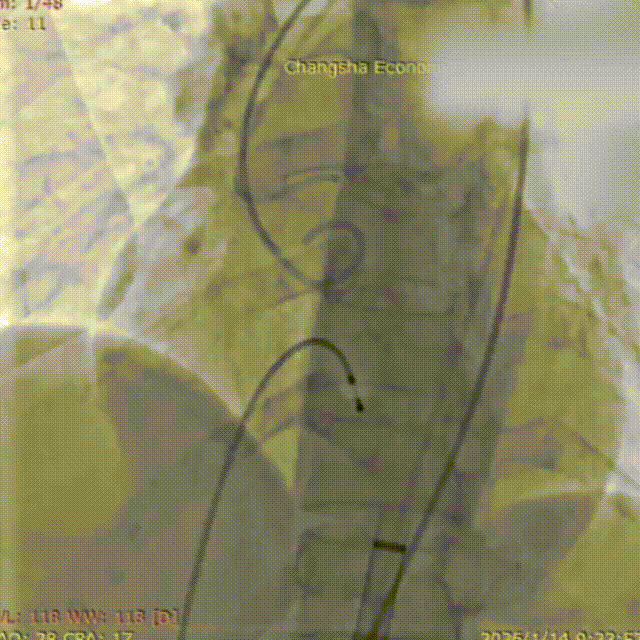

患者取平卧位,在全麻及经食道超声心动图(TEE)和血管造影联合引导下,成功穿刺右侧股动脉,置入20F输送鞘管。穿刺点血管直径5.8mm,入路通畅。猪尾导管下行主动脉根部造影,清晰显示主动脉形态及无返流。在跨瓣过程中,考虑到患者心尖部心肌薄弱,导丝塑形偏大,全程操作轻柔,避免心肌损伤。

主动脉根部造影

18mm球囊预扩